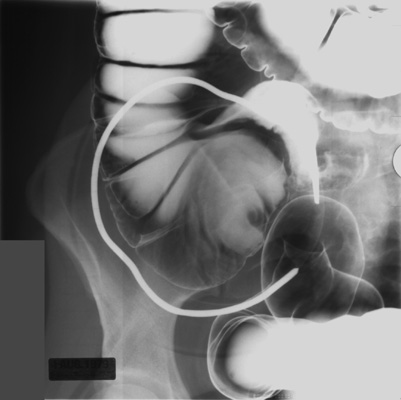

Gastrointestinal Radiology > Procedures > Barium Enema > Double Contrast > Double Contrast (6)

Double Contrast (Air Contrast) Barium Enema (cont.)

Conduct Of The Examination (cont.)

1. Roll the patient supine or RPO. Take a spot image of cecum with graded compression.

1. Turn the patient over to the prone position.

Raise the head of the x-ray table to +45 degrees.

Put the enema bag between the patient's legs, and, for a third time, drain barium from the rectosigmoid.

1. Return the table to a horizontal position.

Add air slowly until the entire colon is well filled. (Let the distension of the transverse colon be your guide.)

Then, have the technologist take overhead radiographs.